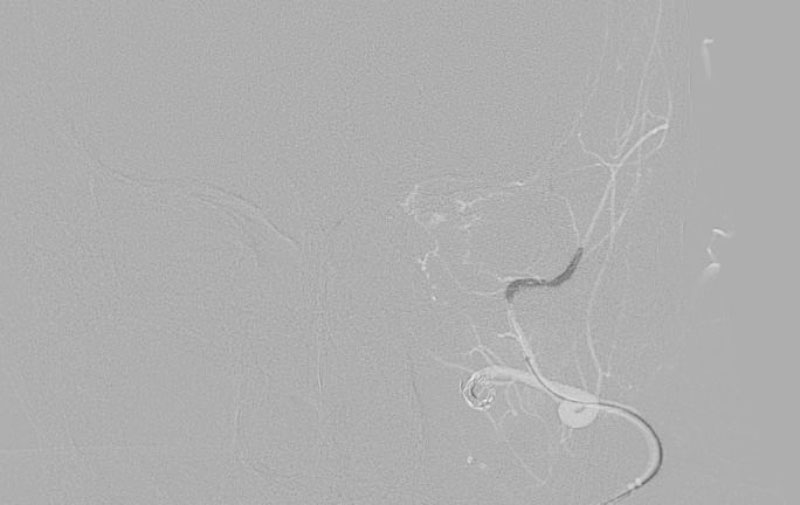

'25年11月

くも膜下出血

破裂性内頚動脈解離

40代

救急外来

No.1594 手術中